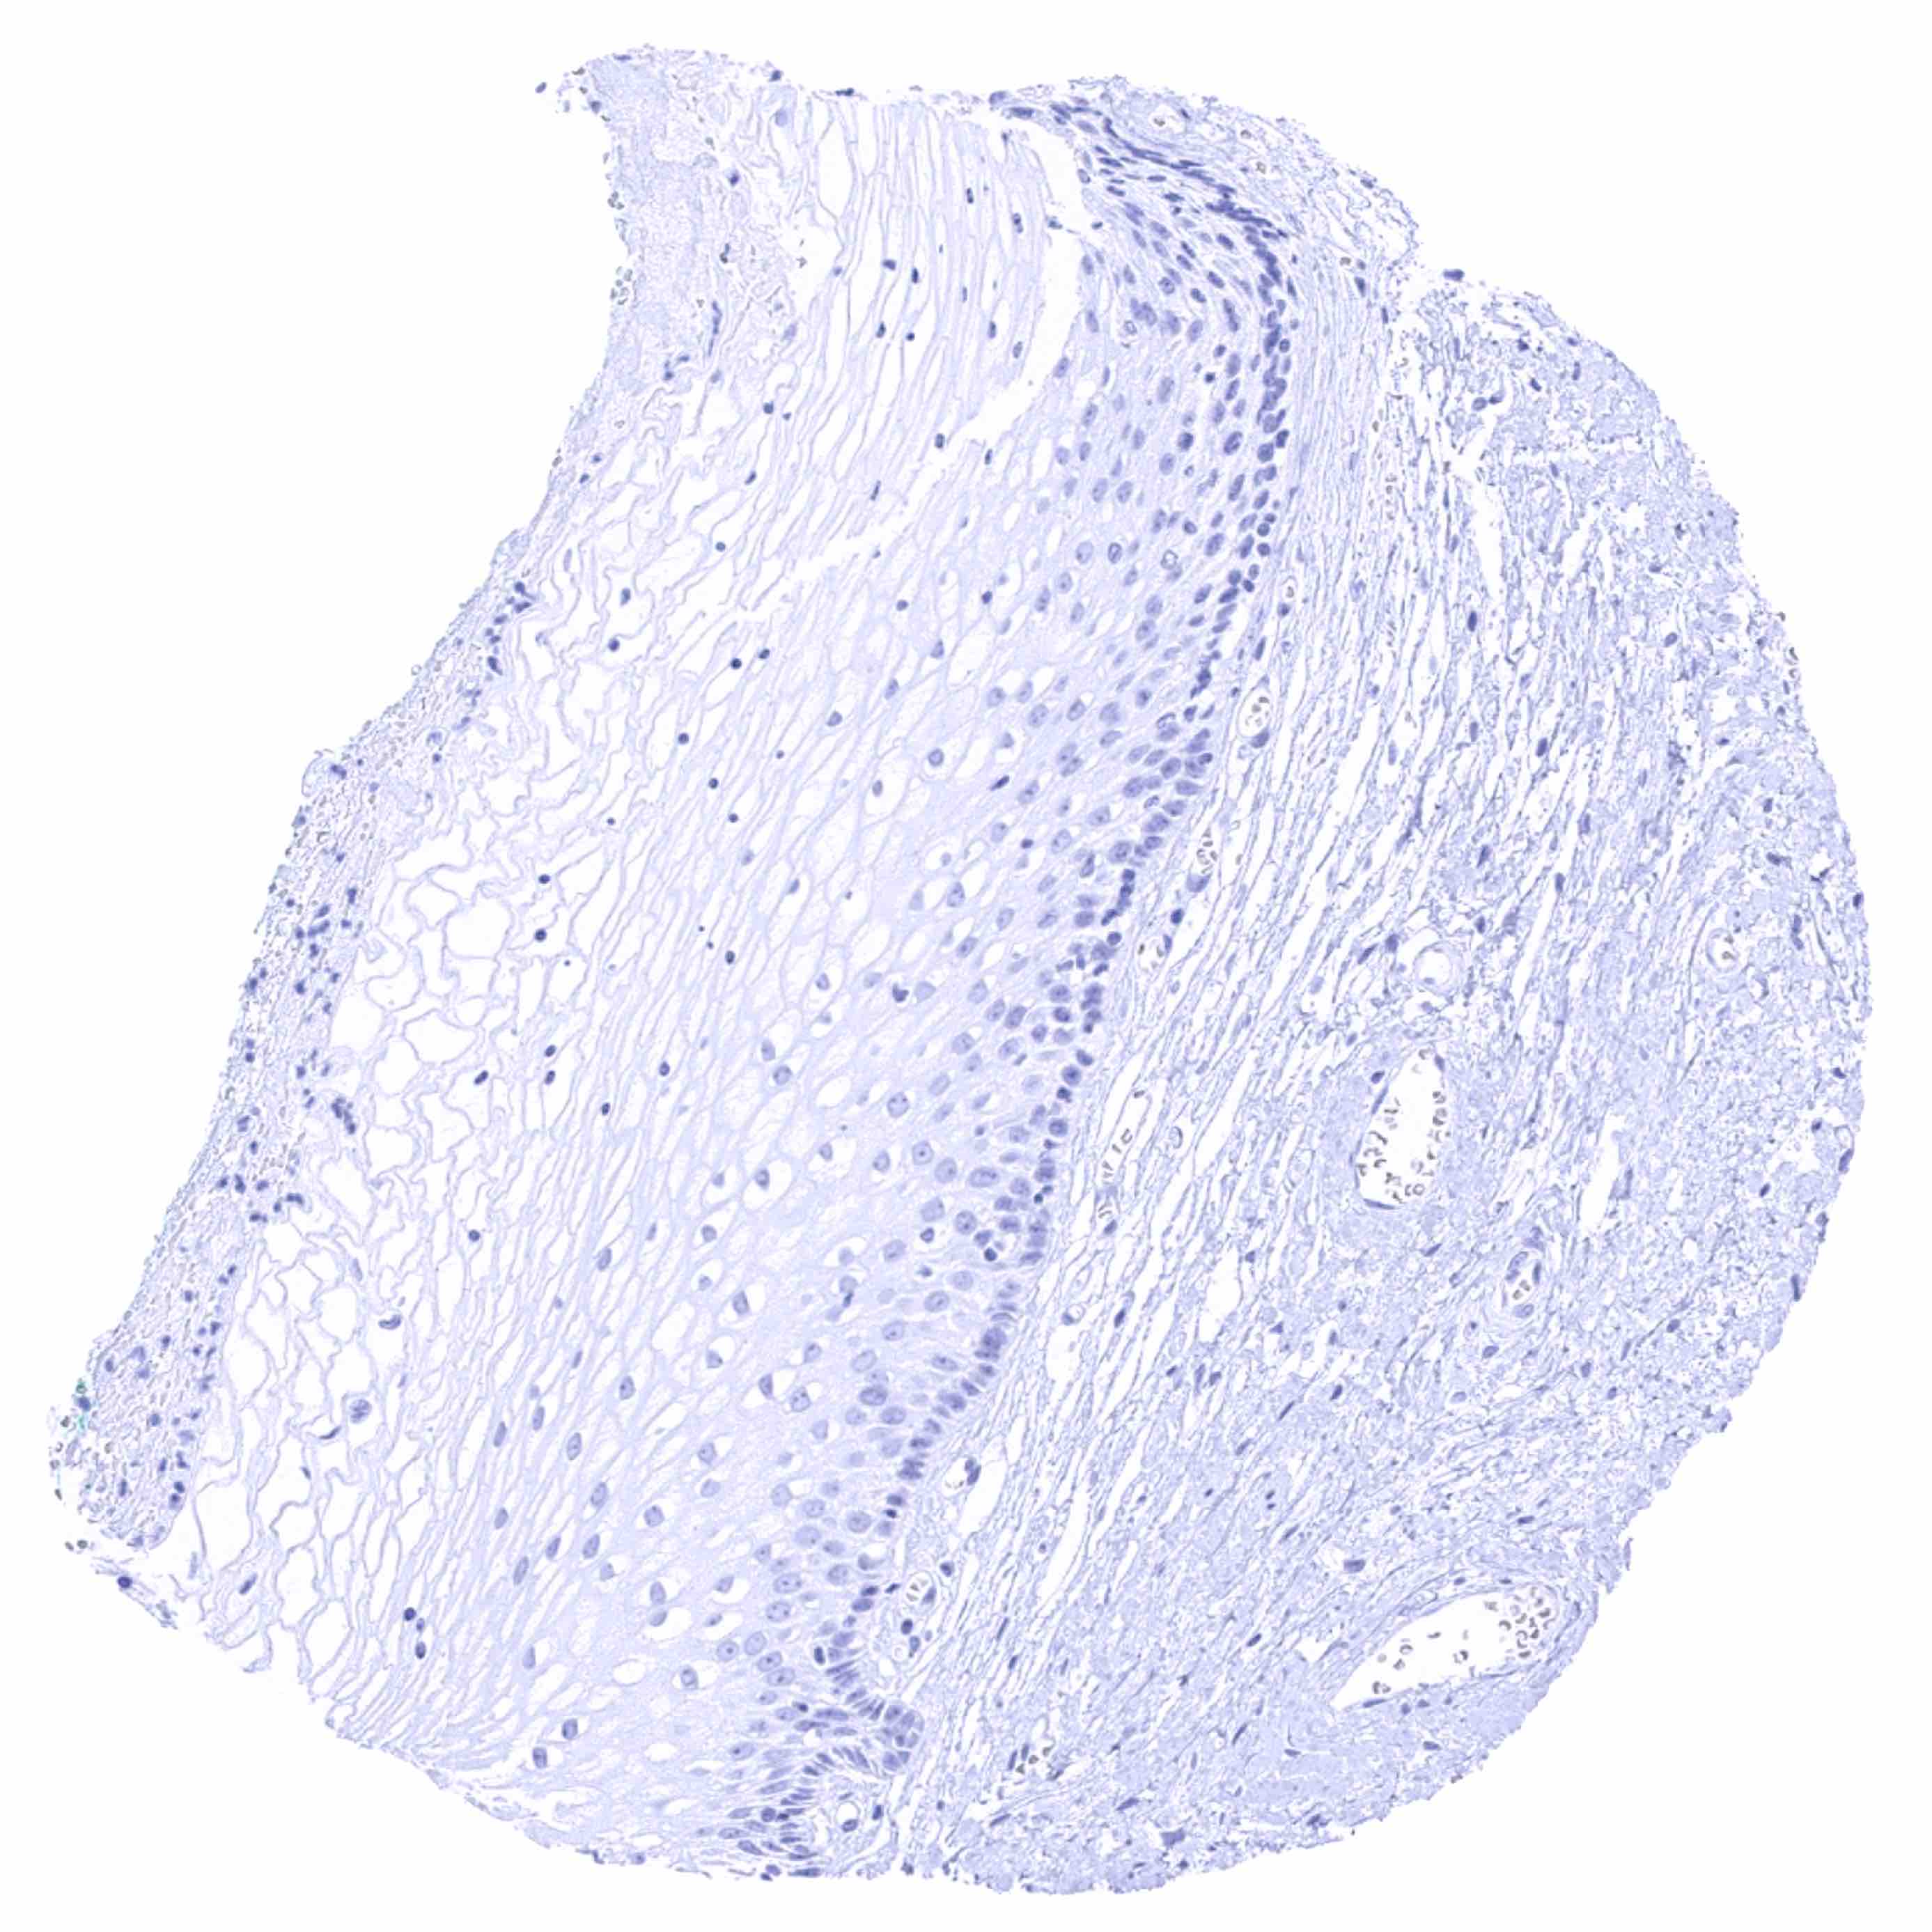

Uterus, ectocervix